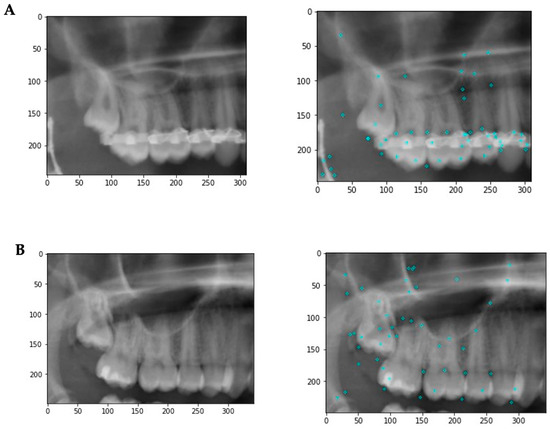

Figure 3.

Example images illustrating some of the image features. (A) Patient has metallic artefacts affecting the keypoint detection and subsequent classification. In addition, other structures such as endodontic fillings, crowns, composite fillings, etc., might affect the classification. (B) A situation with fewer artifacts. The keypoints are more evenly distributed with a focus on the third molar region.